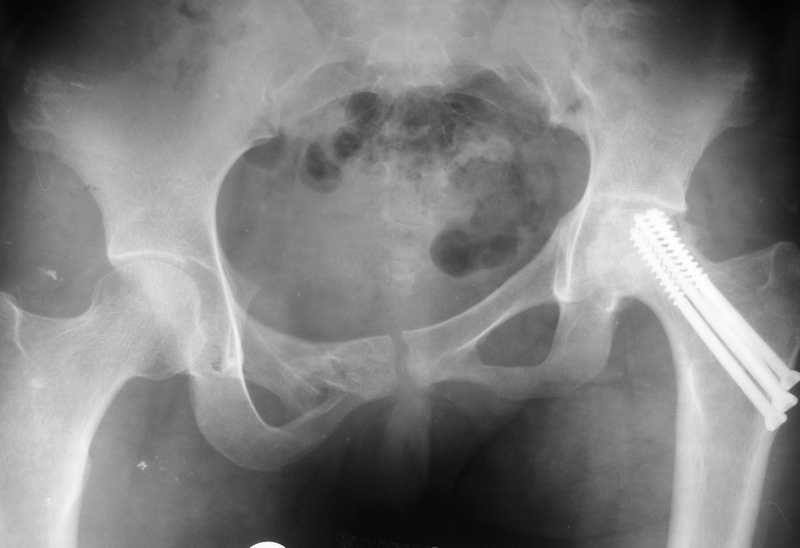

Больная К., 18 лет. Падение с высоты 5 этажа в январе 2008 г.

Остеосинтез винтами перелома шейки бедра слева и оскольчатого перелома

костей таза аппаратом внешней фиксации. Демонтаж аппарата через 3

мес., нагрузка на левую ногу через 6 мес. Через год стала ходить без

палочки. С марта 2009 года стала замечать укорочение левой нижней

конечности, появились боли в левом тазобедренном суставе. В настоящее

время укорочение 8 см., выраженная приводящая контрактура в левом

тазобедренном суставе. На обсуждение выносится тактика: сначала

удлинить конечность, а затем выполнить эндопротезирование или сразу

произвести эндопротезирование.

The patient with posttraumatic AVN of femoral head and fracture of the

pelvis. The trauma was 1,5 year ago. Now she has the pain in the hip

and the shortening 8 cm